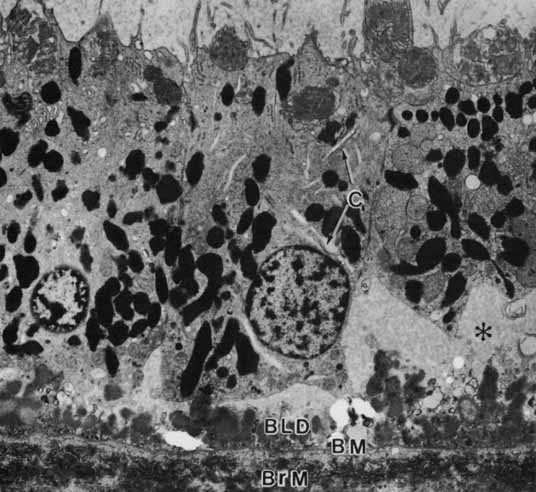

pigmentation. Pigment Cell Res 12:219–236, 1999 65. Schraermeyer U, Peters S, Thumann G, Mociok N, Heiman K: Melanin granules of the retinal pigment epithelium are connected with the

lysosomal degradation pathway. Exp Eye Res 68:237–245, 1999 66. Eldred GE: Lipofuchsin and other lysosomal storage deposits in the retinal pigment

epithelium. In Marmor MF, Wolfensberger TJ, (eds): The Retinal Pigment Epithelium. New York: Oxford University Press, 1998:651–668 67. Feeney-Burns L, Hilderbrand ES, Eldridge S: Aging human RPE: Morphometric analysis of macular, equatorial, and peripheral

cells. Invest Ophthalmol Vis Sci 25:195–280, 1984 68. Wolf G: Lipofuchsin and macular degeneration. Nutr Rev 61:342–346, 2003 69. Boulton M, Dayhew-Barker P: The roles of the retinal pigment epithelium: topographical variation and

ageing changes. Eye 15:384–389, 2001 70. Katz ML, Robison WG: What is lipofuchsin? Defining characteristics and differentiation